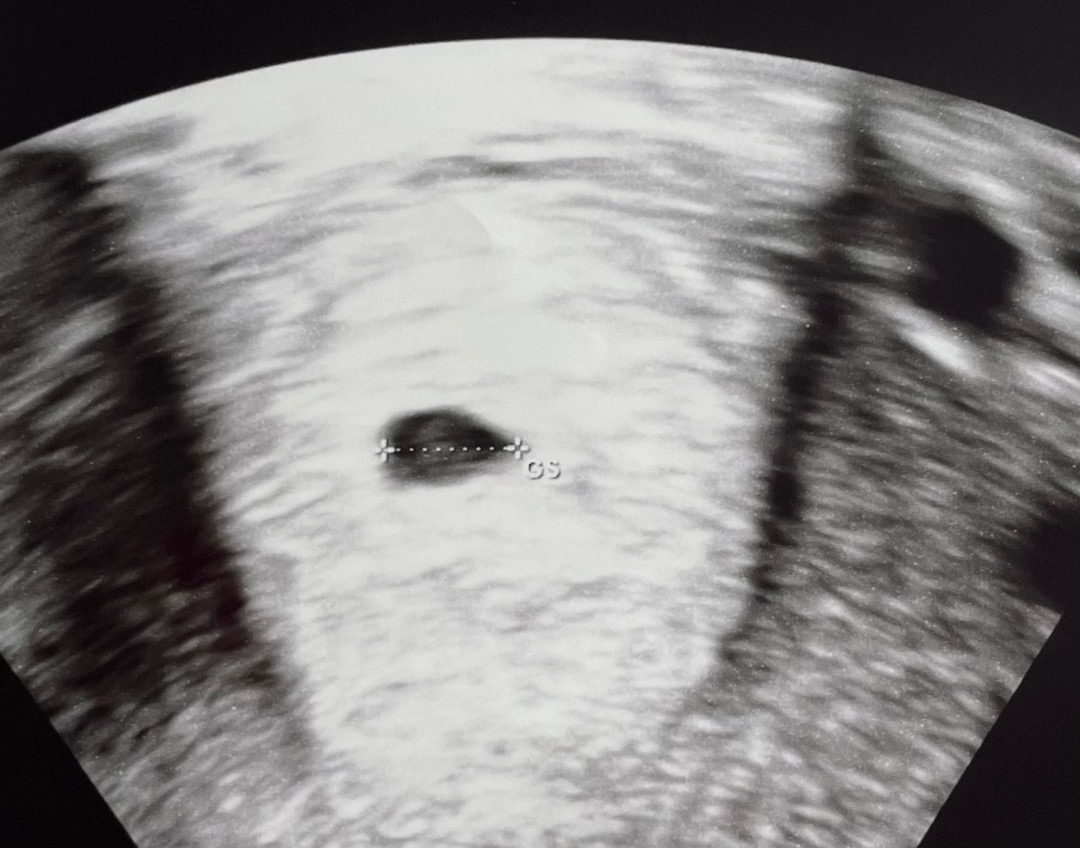

다른 분들 초음파 사진 부러움의 눈팅만 하다가 오늘 드뎌 기다리던 초음파로 애기집 확인했어요~ 감격!! 5주차 초기 정도 됐는데 아직 난황은 안보이신다고 하네요ㅠㅠ애기집만 덩드러니ㅠ 제가 생리주기가 길어서 그런것 같다고 하시는데 괜히 걱정 되네여…난황이 안 생겨서 입덧도 아무 증상도 없었나 싶기듀 하구..ㅎ_ㅎ 잘 있는거지 용용아?? 다음에 또 보자!

저도 전원해서 초음파 두번 봤는데 초반에 굳이 병원 계속 가봐야 아기집도 난황도 시기가 지나야해서 안보인다고들 하더라고요😭 저도 5w6d 인데 난황은 아직 안보여서 이번주 주말에 한번 더 만나러 간답니다😉 입덧은 케바케래요~ 쭉 안할 수도 있고 심할 수도 있고요ㅠㅠ 6주가 지나야 난황이 보이고 6-7주차 되야 심장소리 들리고 한다더라고요🥹